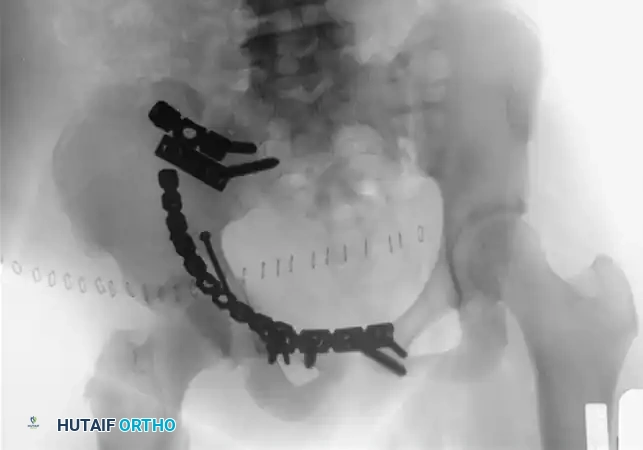

Internal Fixation of the Pubic Symphysis

Once satisfactory reduction is achieved and provisionally held, definitive fixation is applied.

- Plate Selection: Select a multi-hole (typically a six-hole) curved 3.5-mm pelvic reconstruction plate. The curvature should match the superior surface of the pubic symphysis.

- Plate Application: Position the plate on the superior surface of the symphysis.

- Dynamic Compression: Drill the initial holes eccentrically away from the fracture line. As the screws are seated, this will yield a small amount of dynamic compression across the symphyseal fibrocartilage, enhancing stability.

- Double Plating: For highly unstable Tile Type C injuries where posterior fixation is anatomically impossible or medically contraindicated, apply a double plate construct (one superior, one anterior) to maximize stiffness.

- Alternative Approaches: In cases involving extensive pubic rami fractures where the Pfannenstiel approach provides insufficient lateral exposure, transition to a modified Stoppa or an ilioinguinal approach.

💡 Clinical Pearl

Always confirm the final reduction and hardware placement with intraoperative fluoroscopy (AP, Inlet, and Outlet views) before closure. Ensure no screws have penetrated the hip joint or the space of Retzius.

2. Transiliac Rod Fixation and Tension Band Plating

For highly unstable sacral disruptions or comminuted transforaminal fractures where IS screws lack purchase, transiliac fixation is utilized.

- Transiliac Rods: A large Steinmann pin or threaded rod (8 to 10 mm) is drilled from the outer aspect of one ilium, through the posterior elements of the sacrum, and out the opposite ilium. A second rod is often placed 1.5 cm distal and parallel to the first. Warning: Over-compression can cause iatrogenic sacral nerve root crush.

- Tension Band Plating: A reconstruction plate can be contoured and applied posteriorly between the two posterior superior iliac spines (PSIS), acting as a tension band against anterior pelvic opening.